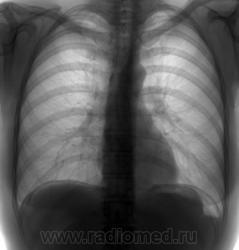

Свободный газ

Вашему вниманию представляется  случай обнаружения свободного газа в брюшной полости при профилактической ФГ. Причина появления непонятна. Предположите, хоть примерно, при какой ситуации....жалоб не предьявляет. Женщина 54 лет.

4. На второй день в другом ЛПУ был проведен контроль по желанию больной - картина прежняя, степень выражености несколько меньше.

Доцент Крамной И.Е. с кафедры рентгенологии ХМАПО, читая лекции по рентгендиагностике неотложных состояний в брюшной полости, смакуя, называет это состояние посткоитуальным пневмоперитонеумом. После того, как хирурги собирались женщину уложить в стационар, она созналась, что действительно "кувыркалась" со своим дедом накануне.

Значит все-таки из маточных труб))))